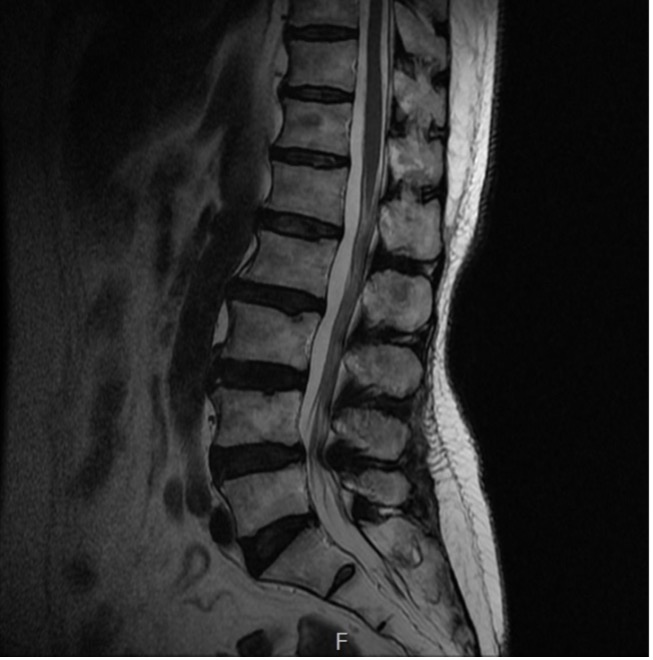

척추관협착증

척추관협착증이란

어떤 원인으로 척추 중앙의 척추관, 신경근관 또는 추간공이 좁아져 허리의 통증의 유발하거나 다리에 여러 복합적인 신경증세를 일으키는 질환

입니다.

디스크를 구성하는 수핵과 섬유륜에 퇴행성 변화가 일어나고 척추관을 구성하는 뼈와 인대 등이 두꺼워져 척추 뼈가 어긋나는 경우 척추 신경을 눌러 통증을 일으킵니다.

증상

· 보행시 허벅지와 종아리에 통증 및 저림증상 발생

· 허리의 심한 통증보다는 묵직한 불편함

· 장시간 보행을 하지 못하고 화끈거리는 느낌

· 다리 전체에 힘이 빠지고 마비가 되는 느낌

· 심할 경우 배뇨, 배변 장애 발생